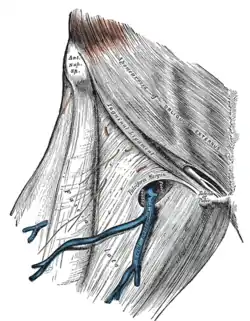

The fossa ovalis. | |

Just inferolateral to the pubic tubercle the fascia extends downwards forming an arched (falciform) margin of the lateral boundary of the opening. It is covered by a thin perforated part of the superficial fascia called the fascia cribrosa which is pierced by the great saphenous vein, the 3 superficial branches of the femoral artery(except superficial circumflex iliac artery, which pierces fascia lata lateral to the saphenous opening), and lymphatics.

The fascia cribrosa, which is pierced by the structures passing through the opening, closes the aperture and must be removed to expose it.

The great saphenous vein and its tributaries at the fossa ovalis.